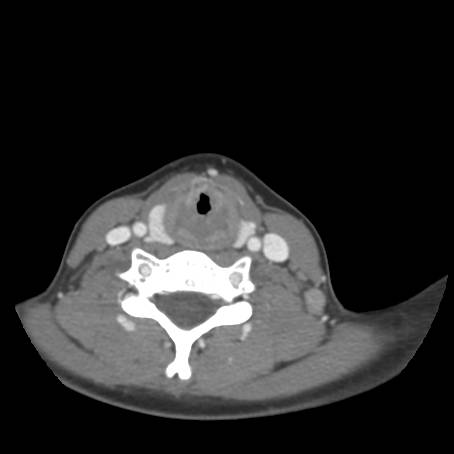

Fig.4a - normal epiglottis and arytenoids; Fig.4b - normal vocal cords, fullness seen below cords; Fig.4c - irregular mucosa in subglottic space with stenosis; Fig.4d-f - normal trachea below subglottic space with normal subsegmental bronchi (blood seen is iatrogenic related to procedure)

![]() Figure 5a |

![]() Figure 5b |

![]() Figure 5c |

Describe CT.